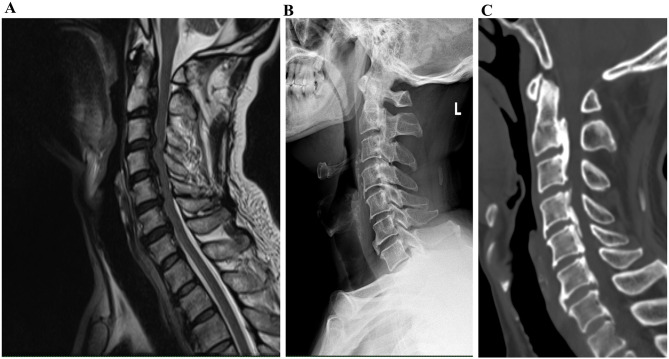

多形性红斑是一种皮肤和粘膜炎症性疾病,主要由病毒感染引起,表现为各种形态的斑块。我们提出的情况下,59岁的男子谁发展为瘙痒皮疹,他的身体后7天颈椎单开门脊柱减压手术。他没有病毒性皮疹的病史。他接受了抗生素和抗过敏治疗,但症状没有缓解。怀疑是病毒感染,开始使用抗病毒药物。皮疹消退后,炎症标志物继续升高,伴高热,怀疑继发性细菌感染。开始使用美罗培南,病人的生命体征恢复正常。这是一个罕见的病例多形性红斑和继发的细菌感染后颈椎手术。根据我们的研究结果,在以下情况下,建议对颈椎手术后病毒感染的患者进行抗菌治疗:获得的血培养未证实细菌感染,而患者的病程和感染指数升高怀疑是细菌感染。

Erythema multiforme, an inflammatory skin and mucosal condition, is mainly caused by a viral infection and presents as plaques of various morphologies. We present the case of a 59-year-old man who developed a pruritic rash all over his body seven days after posterior cervical single-open-door spinal decompression surgery. He had no history of a viral rash. He received antibiotics and anti-allergic treatment without relief of symptoms. Suspecting a viral infection, antivirals were started. While the rash subsided, the inflammatory markers continued to increase, accompanied by hyperpyrexia, leading to the suspicion of secondary bacterial infection. Meropenem was started, and the patient's vital signs returned to normal. This is a rare case of erythema multiforme and secondary bacterial infection following cervical spine surgery. Based on our findings, antimicrobial therapy is recommended for patients with viral infection after cervical spine surgery in the following situations: bacterial infection was not confirmed by the blood cultures obtained, and was suspected by the patients' course and elevated infection indices.